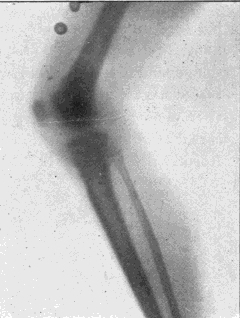

Fig. 2.—Broken Arm, Overlapping.

(Due to defective setting.)